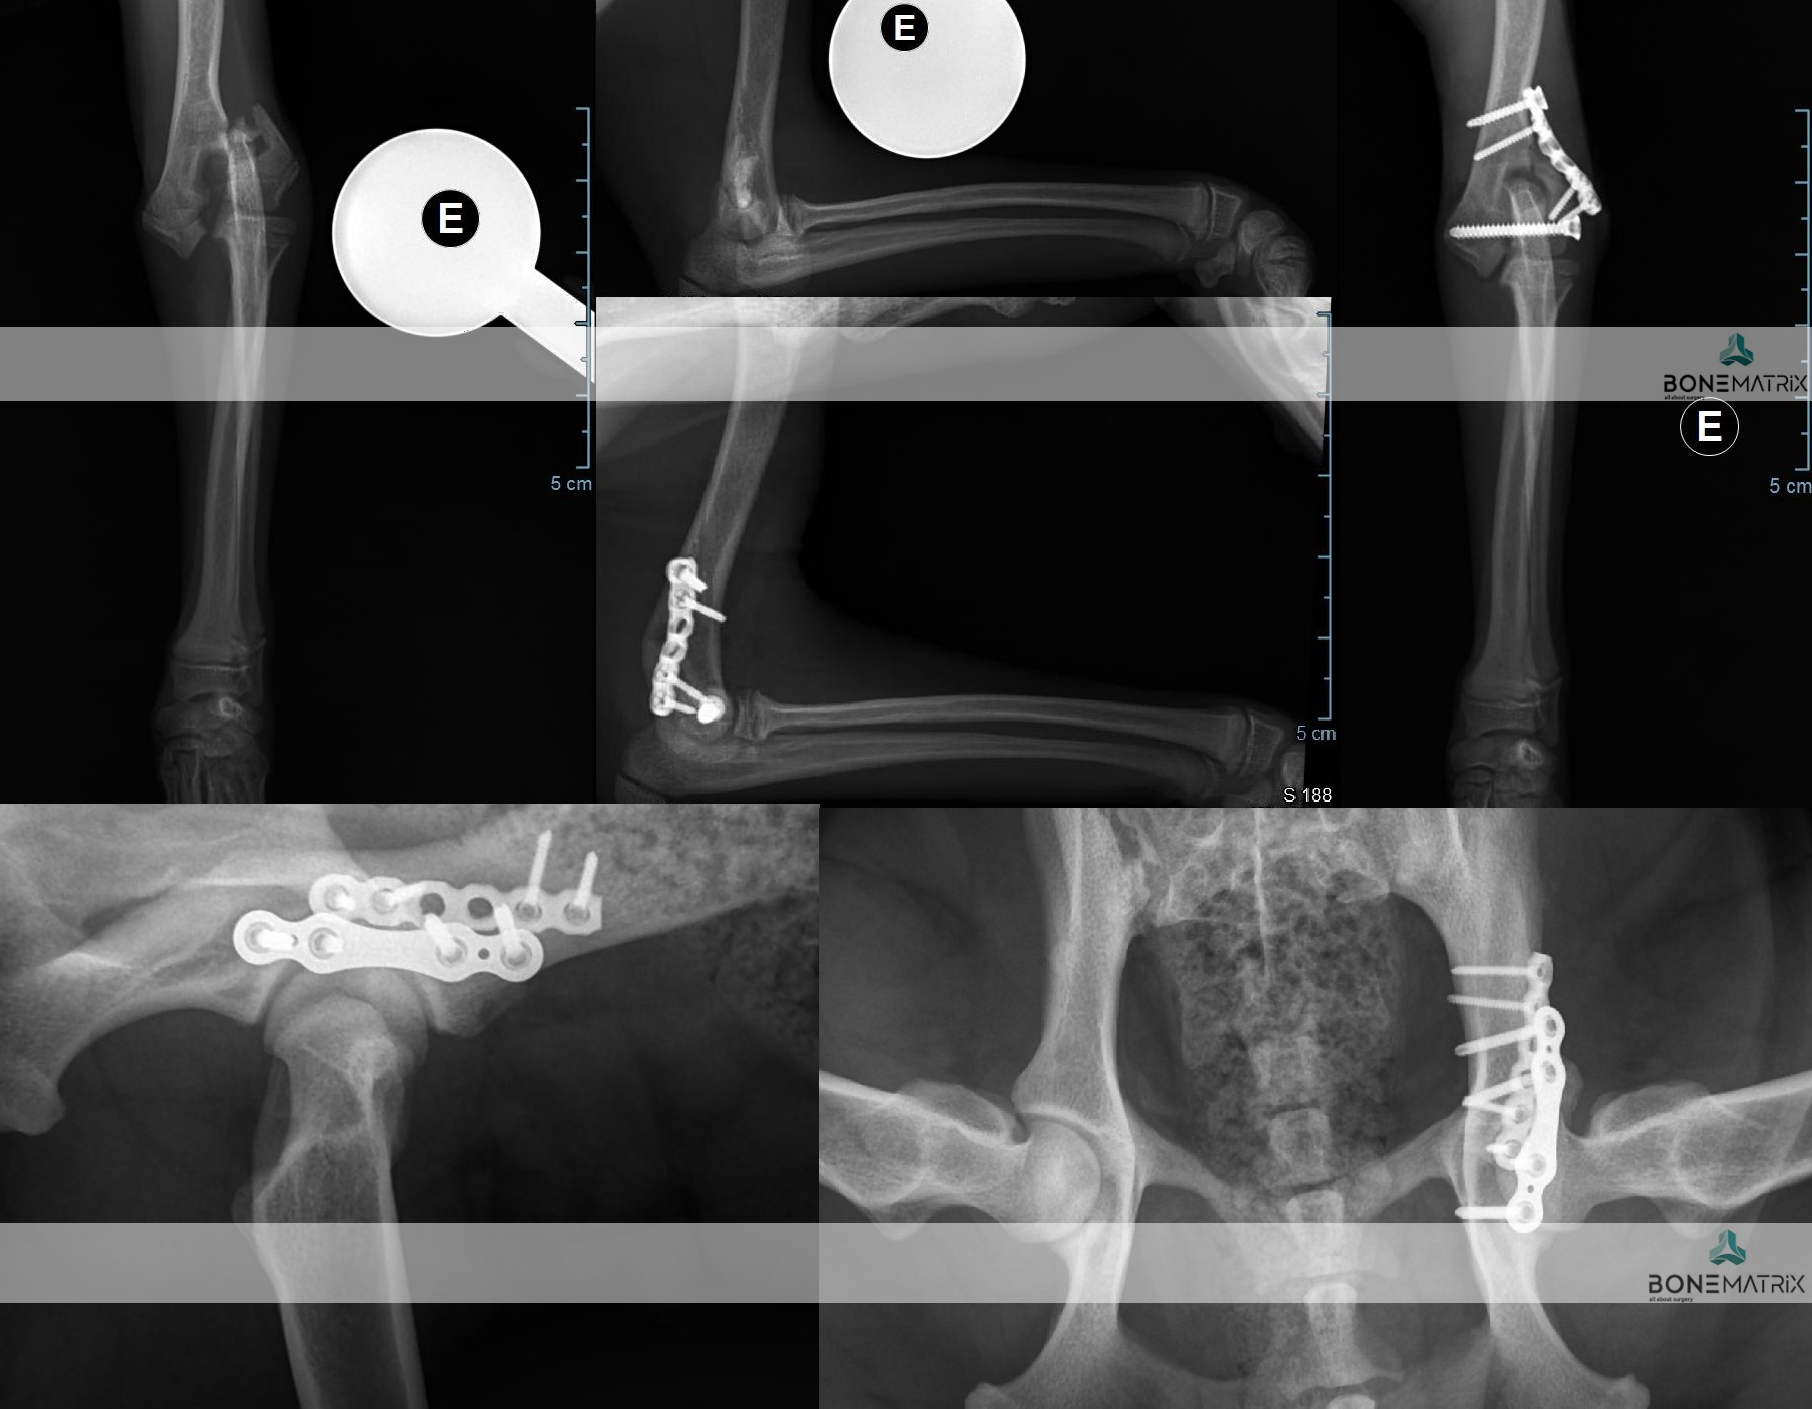

O que é?

DFO (distal femoral osteotomy) é um procedimento realizado como parte integrante ou abordagem única à patologia de luxação de patela (rótula).

A realização desta cirurgia implica a realização pré-cirúrgica de um planeamento cirúrgico baseado num estudo radiográfico.

No estudo realizado são feitas medições de vários ângulos relacionados com o alinhamento do membro posterior. Estes ângulos influenciam a direção sob a qual é exercida força sobre o joelho, podendo conduzir à luxação de patela.

Caso exista uma deformidade angular no fémur, é aconselhada a correção do ângulo em causa através da técnica DFO, para que a patela consiga permanecer alinhada na sua localização anatómica (sulco troclear).

A técnica consiste na realização de dois cortes no osso, para correção do defeito angular, e posterior estabilização dos cortes feitos com recurso a placas e parafusos bloqueados (implantes com um grau de segurança superior).

PTO (proximal tibial osteotomy) é um procedimento cirúrgico utilizado para correção de deformidades angulares presentes na tíbia.

A realização deste procedimento exige um estudo radiográfico com planeamento cirúrgico anterior ao procedimento cirúrgico. Neste são medidos ângulos relacionados com o alinhamento do membro posterior.

A cirurgia consiste na realização de dois cortes, previamente planeados, na tíbia, seguindo-se a sua estabilização por meio de placa e parafusos bloqueados (estes implantes apresentam um alto grau de segurança na sua utilização).

Dada a versatilidade desta técnica, várias patologias podem ser corrigidas com esta abordagem, nomeadamente luxações de patela e outras deformidades do membro posterior.

Nesta cirurgia também são utilizadas com frequência guias 3D que definem o local de corte com elevada precisão. Estas guias são planeadas a partir de imagem de TAC em softwares de especialidade e seguidamente são produzidas no nosso laboratório 3D, de forma a estarem adaptadas as características individuais de cada paciente.

A TTT (tibial tuberosity transposition) é uma técnica cirúrgica que pode ser utilizada como componente única ou integrada nos procedimentos necessários para a correção de luxação de patela.

A TTT consiste na realização de um corte ao nível da tíbia que altera a posição do tendão patelar (inserido na tuberosidade tibial).

Ao movimentar esta estrutura vamos alterar o angulo de inserção do tendão patelar e movimentar por consequência a patela (rótula) para a sua posição anatómica (dentro do sulco troclear).

A nova posição que pretendemos que seja assumida pela tuberosidade tibial é fixada por meio de um K-wire (implante cirúrgico).

Porque é necessário a aplicação desta técnica cirúrgica?

DPO (double pelvic osteotomy) é um procedimento preventivo realizado em pacientes onde o despiste de displasia de anca prevê o desenvolvimento desta doença.

Inicialmente deve ser realizado um despiste de displasia de anca com recurso a um estudo radiográfico especifico para que o paciente seja avaliado e seja definido como um bom candidato à aplicação desta técnica.

A DPO consiste na realização de dois cortes ao nível da pélvis que permitem a rotação do fragmento criado. Este fragmento inclui a porção articular da pélvis, na articulação coxofemoral (o acetábulo).

Ao rodar este fragmento conseguimos uma maior cobertura da cabeça femoral pelo acetábulo, impedindo o movimento de saída da cabeça femoral de dentro do acetábulo. Ao impedir este movimento (laxitude articular) impedimos o desenvolvimento de lesões de osteoartrite provocada por ele, e desta forma impedimos o desenvolvimento da doença de displasia de anca.

Após rotação do fragmento, este é estabilizado na posição pretendida com recurso a placas bloqueadas especializadas para a realização desta cirurgia, garantindo assim a cicatrização do osso no ângulo previamente definido.